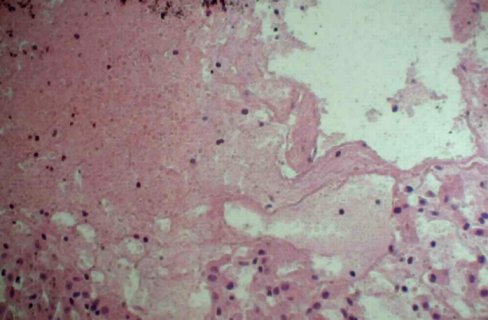

(二)发病机制

家族性地中海热患者缺乏1种可对抗补救途径的炎症媒介C5a并抑制中性粒细胞趋化的蛋白质,Con-A诱导的抑制降低,C5a抑制物在患者滑膜和腹膜液中缺乏。本病发作时IL-1、TNF易于“耗尽”。在非中欧犹太人中导致家族性地中海热的基因主要在染色体短臂16号上,高携带频率的家族性地中海热基因增加了后代得病的概率而并非纯合子。